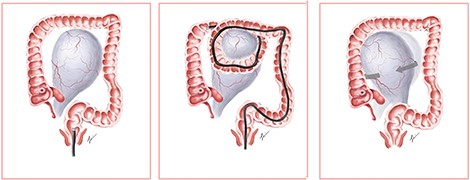

A diagnosis of right ovarian torsion was made and the patient underwent exploratory laparotomy, right salpingo-oophorectomy with intra-operative frozen section and omentectomy. Intra-operatively, torsion of right gonadal vessels was noted (Fig. 2). The right gonadal vessels were taken between ties. The right fallopian tube was ligated. Frozen section from the right salpingo-oophorectomy showed features of benign serous cystadenoma with extensive haemorrhagic infarction in keeping with torsion. There was no evidence of malignant cells. Omentectomy was performed and sent for frozen section, which returned with no evidence of malignancy. The abdominal cavity was washed thoroughly and closed with sutures.

We propose a postulated mechanism of ovarian torsion in this patient (Fig. 3). Due to the large size of the ovarian mass, looping during colonoscopy could have caught the ovarian mass between the bowels, leading to the twisting of the mass on its pedicle by the looped segment of the bowel. Application of abdominal compression to advance the endoscope could have precipitated further twisting of the mass, resulting in ovarian torsion. Although causality between colonoscopy and ovarian torsion cannot be proven, the development of acute abdominal pain shortly after colonoscopy prompts us to consider that the colonoscope could have mechanically twisted the ovary on its pedicle.